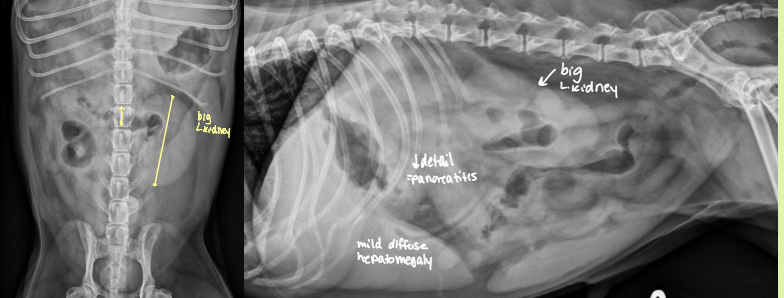

6 reasons for generalized increase in kidney size

hydronephrosis - can be severe

acute inflam

toxic renal

neoplasia